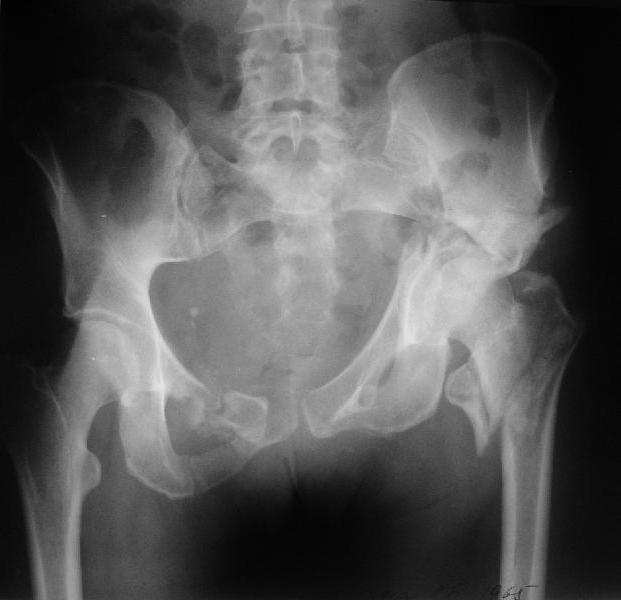

Больная 43 года (промышленный альпинист), 28.07.08 в результате падения с 5 этажа получила политравму: Перелом свода и основания черепа. Вертикально-нестабильное повреждение таза, осложнённое разрывом мочевого пузыря. Чрезвертельный перелом левого бедра. Перелом правой таранной кости, переломовывих правой кубовидной кости. Тупая травма живота, разрыв печени, ушиб почек. Забрюшинная гематома. В день травмы - лапаротомия, ушивание ран печени. Разрыв мочевого пузыря не диагностирован. Течение болезни осложнилось развитием мочевого затёка и обширной пред- и забрюшинной флегмоны, сформировался свищ мочевого пузыря. 19.8.2008 вскрытие, дренировние флегмоны, ревизия мочевого пузыря, обтурация мочевого свища (свищ закрылся в октябре), 1.10.2008 некрэктомия, пластика по Шеде-Лидскому правой кубовидной кости. По результатам КТ диагностирован рак правой почки (диагностическая находка), 8.10.2008 нефрэктомия справа. Переломы велись консервативно. Имеется вертикальное смещение левой половины таза с выраженным отведением крыла (клинически подвижности нет), несросшийся низкий двухколонный перелом левой вертлужной впадины с потерей конгруэнтности, укорочение около5 см, застарелый разрыв лонного сочленения, неправильно сросшиеся переломы обеих ветвей правой лонной кости с укорочением, патологическая подвижность лоно-седалищного фрагмента слева. Правая нижняя конечность неопорна, несмотря на то, что лежа прямую ногу поднимает, ходит на левой ноге (ортопедическая обувь) с костылями, справа тазобедренный ортез. Седалищные нервы работают.Урологи отпустили больную на 6 мес.

Мучаемся мыслями - как все это заставить ходить.Возможно ли первичное протезирование если просто синтезировать лонное сочленение с цементом и ванкомицином? Если делать большую реконструкцию, то с чего начать? Изрубить крыло и заполнить дефекты? Перерубить боковую массу и попытаться развернуть крыло обратно? Ждать год после закрытия свищей?